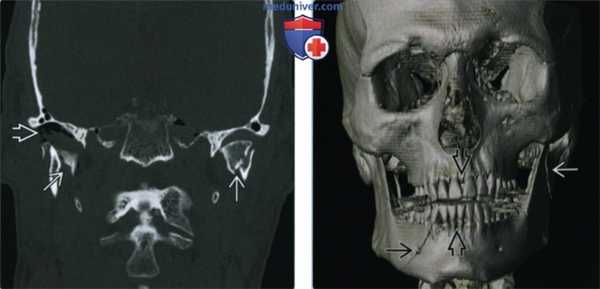

(Слева) При КТ в корональной проекции с обеих сторон определяются переломы мыщелков нижней челюсти; справа наблюдается выраженное смещение отломков. Воздух в правом височно-нижнечелюстном суставе указывает на тяжелые повреждения последнего.

(Справа) При 3D реформатировании определяются косые переломы, идущие через правое подбородочное отверстие и левую ветвь нижней челюсти. Отмечается нарушение смыкания зубов. 3D реформатированные изображения зачастую информативны при планировании хирургического лечения переломов лица.